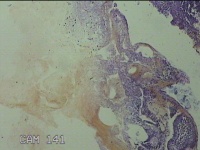

宫腔内容物

性别

女

年龄

45岁

临床诊断

子宫内膜息肉

一般病史

月经量增多10年,B超检查发现宫腔异常回声半月余。

标本名称

大体所见

灰白暗红色不规则碎组织1.5x1.3x0.7cm一堆。

图2